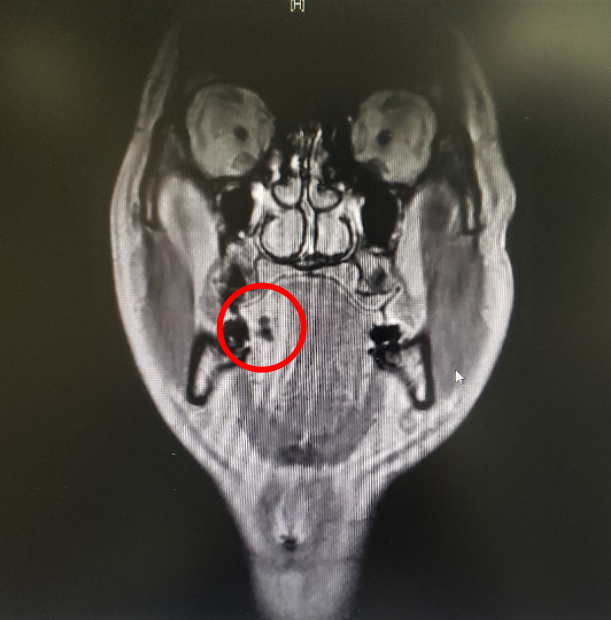

图一:患者的MRI

图二:患者的MRI

图三:患者的MRI

图四:病人的术前MRI

那么这个异物包裹性脓肿里面到底是什么呢?我猜测要不是鸡骨,要不就是鱼刺,但鸡骨的话体积比较大,在CT上一般能看得出来,而且这么大的鸡骨插进舌头,病人的症状会非常明显,不会等到几个月后才来就诊。而鱼骨一般是很纤细的,在CT上是看不出来的,不过我们仔细看影像的话,还是可以在切面上发现小的阻射影的。